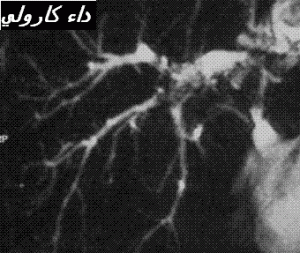

1 – التوسع الأصلي الجيني للقنوات الصفراوية داخل الكبد (20) ( كثيرا ما تمسي مصحوبة بتوسيع القناة الصفراوية الرئيسية) . و تعتقد هاته الحالة شائعة نسبيا في البلدان الأسيوية و استثنائية في الغرب تحت شكل داء كرولي (21)

Maladie de Caroli